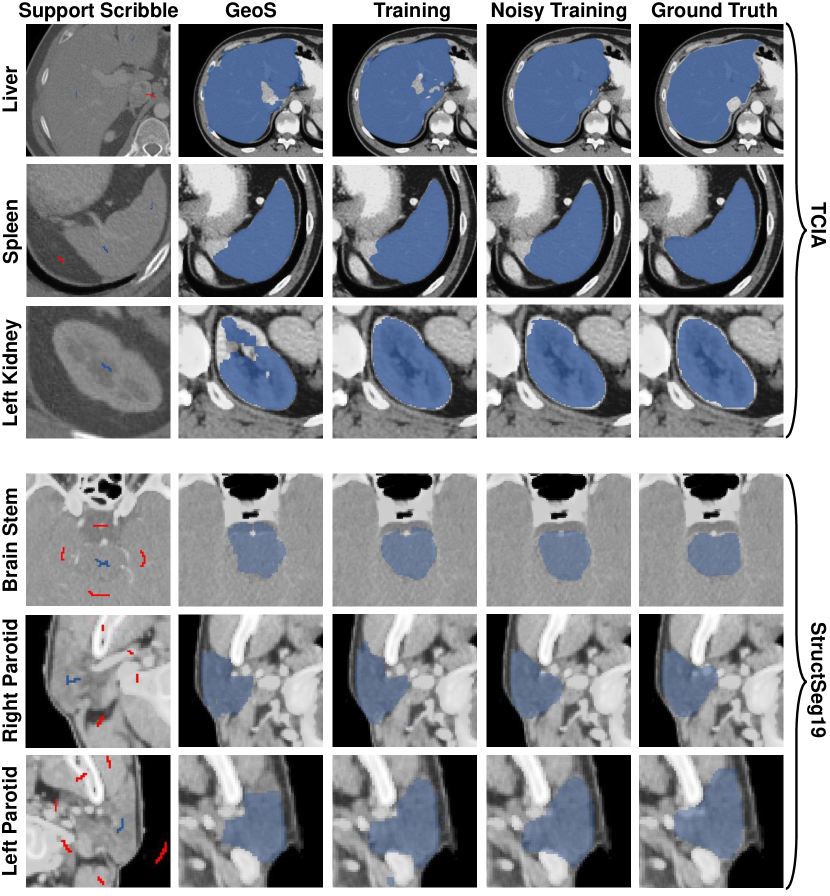

Refer to caption

Figure 8: Examples of predictions under different stages.

To show the necessity and advantages of the noisy training, we conduct experiments training fθsubscript𝑓𝜃f_{\theta} with and without PLC, shown in Table 3. From the table, we can observe that fθsubscript𝑓𝜃f_{\theta} brings a 3.8% and 6.6% improvement in TCIA and StructSeg19 compared to the pseudo masks. This implies that even without any specific setting, deep CNNs are robust to strong label noise. With iterative label cleaning, PLC brings an extra 6.8% improvement in TCIA and 0.5% in StructSeg19.

Fig. 8 shows segmentation examples under different settings. It could be noted that even with very sparse support annotations, our training model could yield precise results.